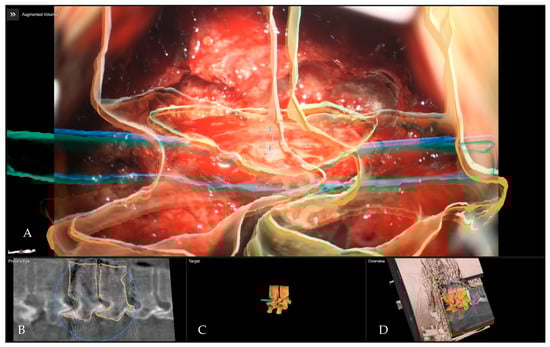

- Pojskić, M.; Bopp, M.; Saß, B.; Kirschbaum, A.; Nimsky, C.; Carl, B. Intraoperative Computed Tomography-Based Navigation with Augmented Reality for Lateral Approaches to the Spine. Brain Sci. 2021, 11, 646. [Google Scholar] [CrossRef] [PubMed]

- Carl, B.; Bopp, M.; Saß, B.; Pojskic, M.; Nimsky, C. Augmented reality in intradural spinal tumor surgery. Acta Neurochir. 2019, 161, 2181–2193. [Google Scholar] [CrossRef] [PubMed]

- Carl, B.; Bopp, M.; Saß, B.; Pojskic, M.; Voellger, B.; Nimsky, C. Spine Surgery Supported by Augmented Reality. Glob. Spine J. 2020, 10 (Suppl. 2), 41S–55S. [Google Scholar] [CrossRef]

- Carl, B.; Bopp, M.; Saß, B.; Voellger, B.; Nimsky, C. Implementation of augmented reality support in spine surgery. Eur. Spine J. 2019, 28, 1697–1711. [Google Scholar] [CrossRef]

- Carl, B.; Bopp, M.; Saß, B.; Nimsky, C. Microscope-Based Augmented Reality in Degenerative Spine Surgery: Initial Experience. World Neurosurg. 2019, 128, e541–e551. [Google Scholar] [CrossRef] [PubMed]